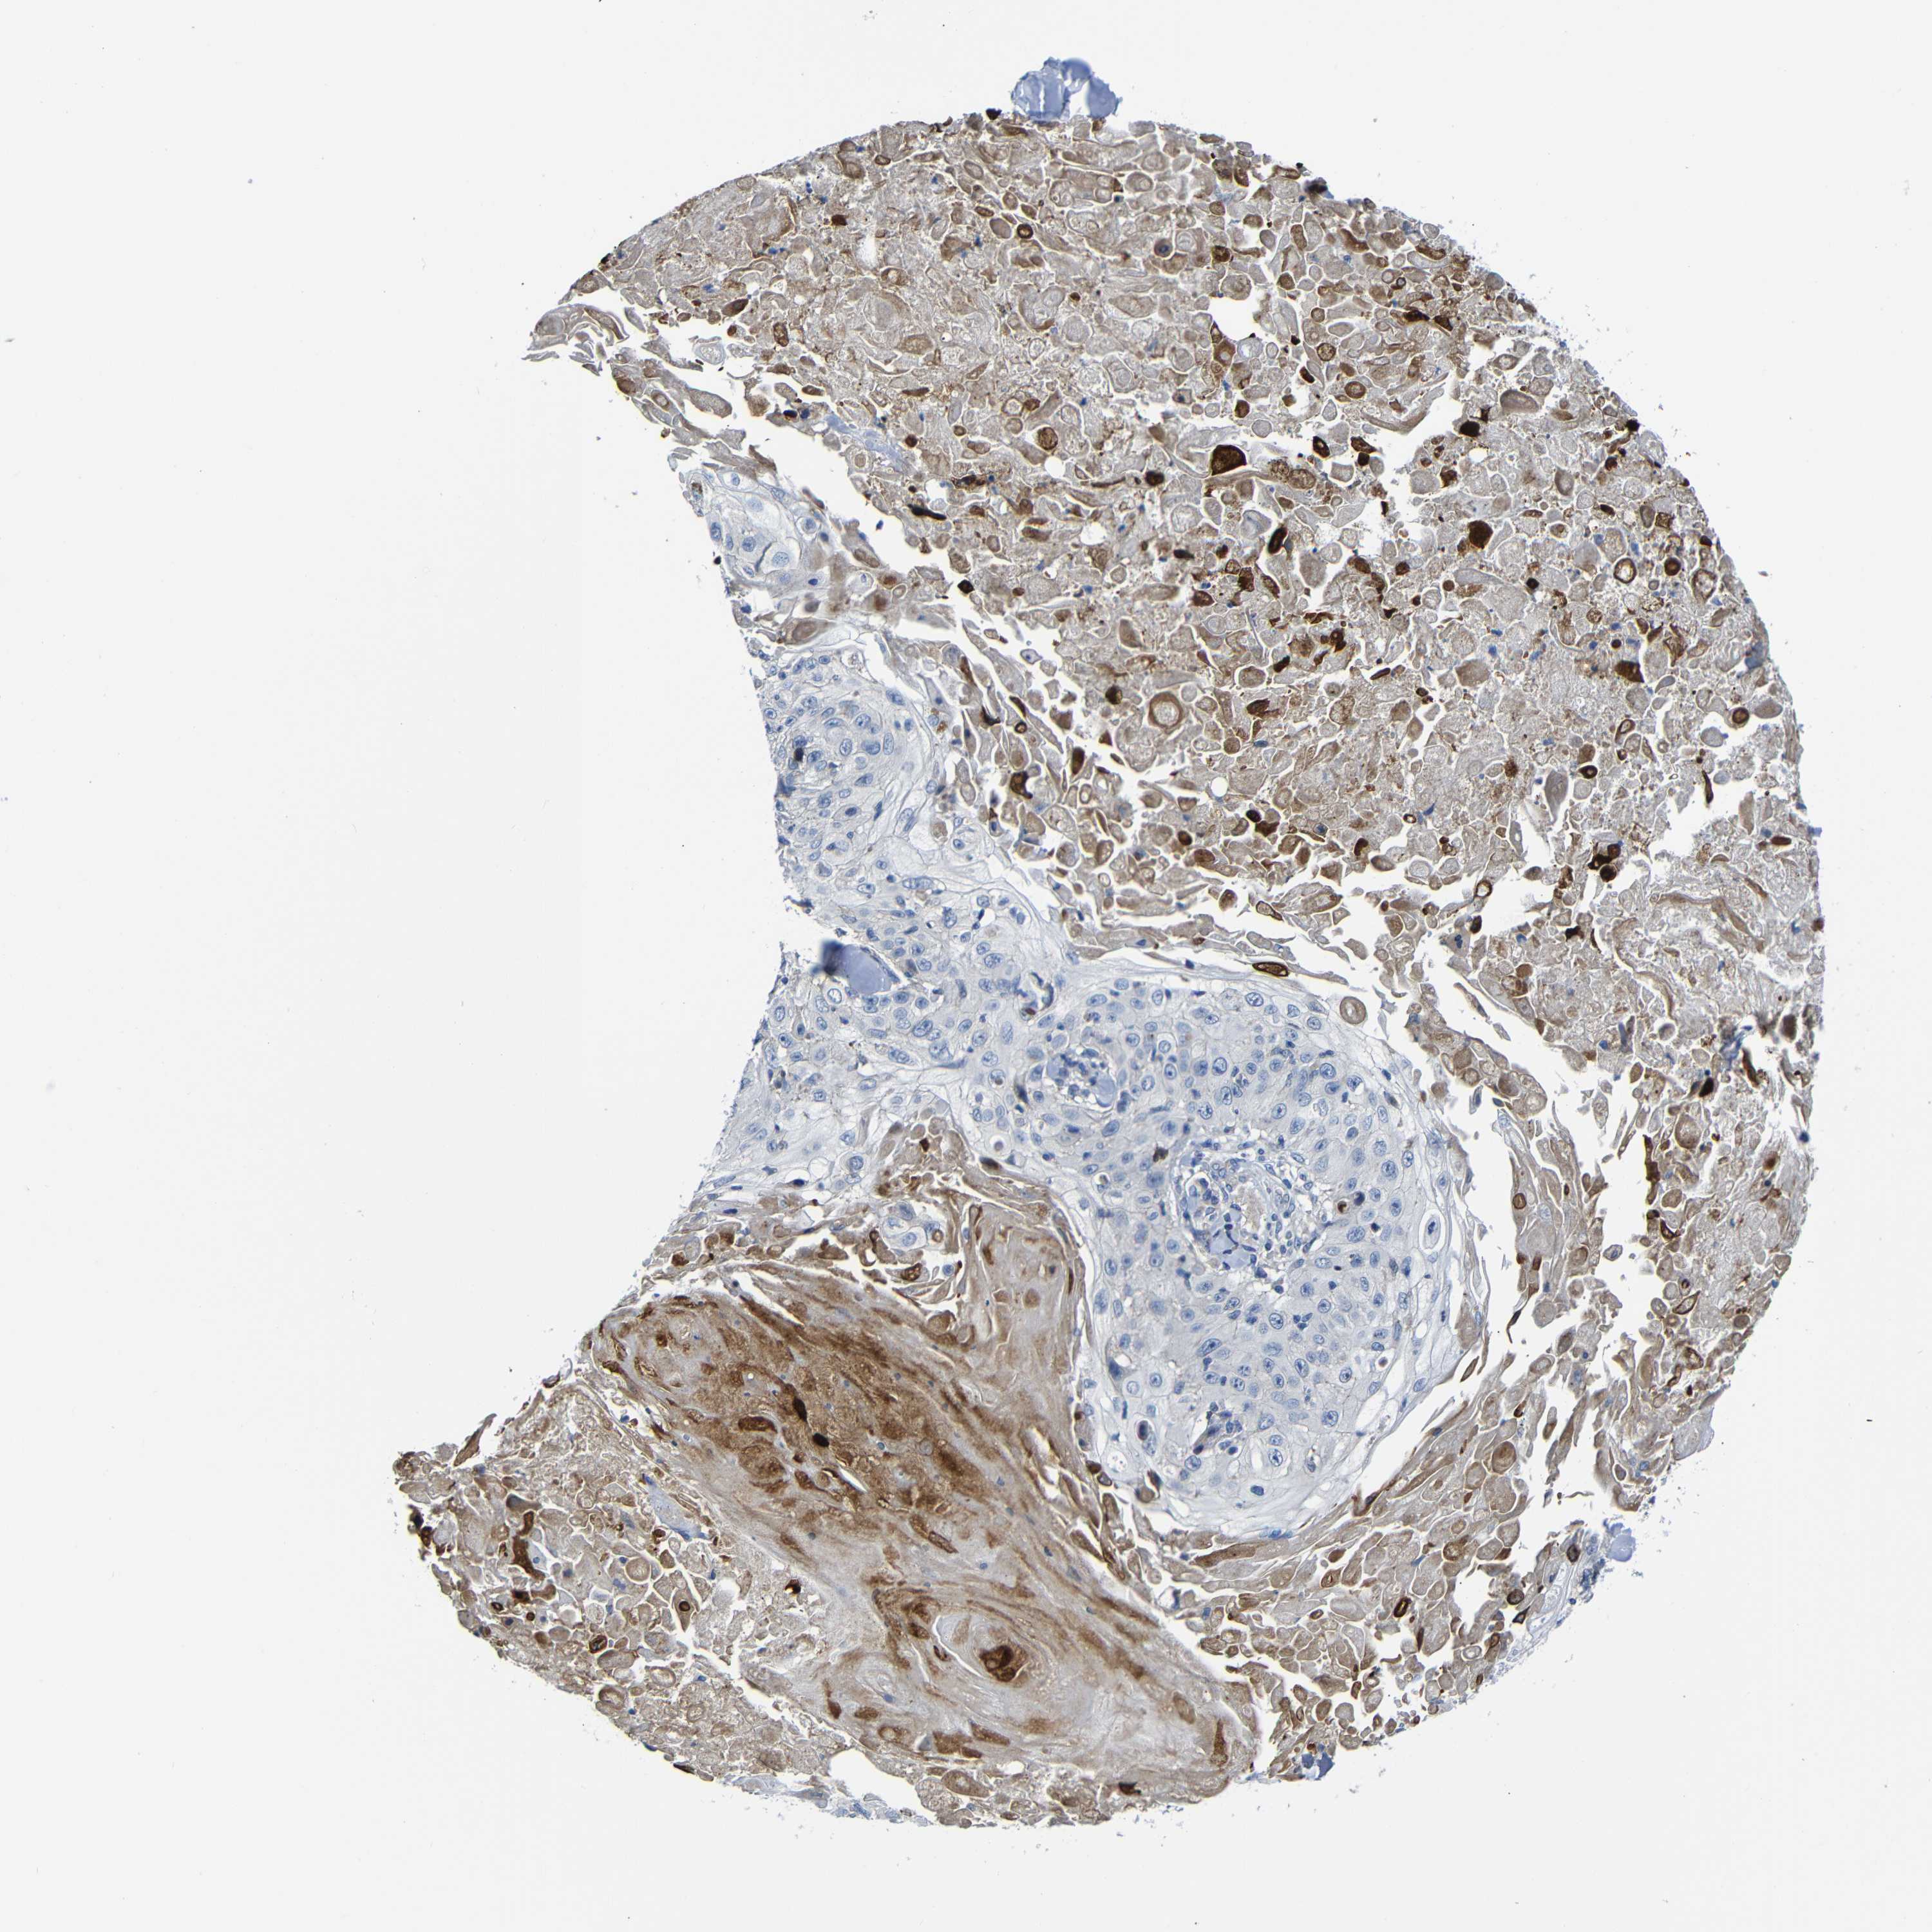

SKIN CANCER - Protein expressioni

A mouse-over function shows sample information and annotation data. Click on an image to view it in a full screen mode. Samples can be filtered based on level of antibody staining by selecting one or several of the following categories: high, medium, low and not detected. The assay and annotation is described here.

Antibody staining in the annotated cell types in the current human tissue is reported as not detected, low, medium, or high, based on conventional immunohistochemistry profiling in selected tissues. This score is based on the combination of the staining intensity and fraction of stained cells.

Each image is clickable and will lead to virtual microscopy that enables deeper exploration of all samples and also displays staining intensity scores, fraction scores and subcellular localization as well as patient and tissue information for each sample.

Basal cell carcinoma

Squamous cell carcinoma, NOS

Squamous cell carcinoma, metastatic, NOS

Adnexal tumor, benign